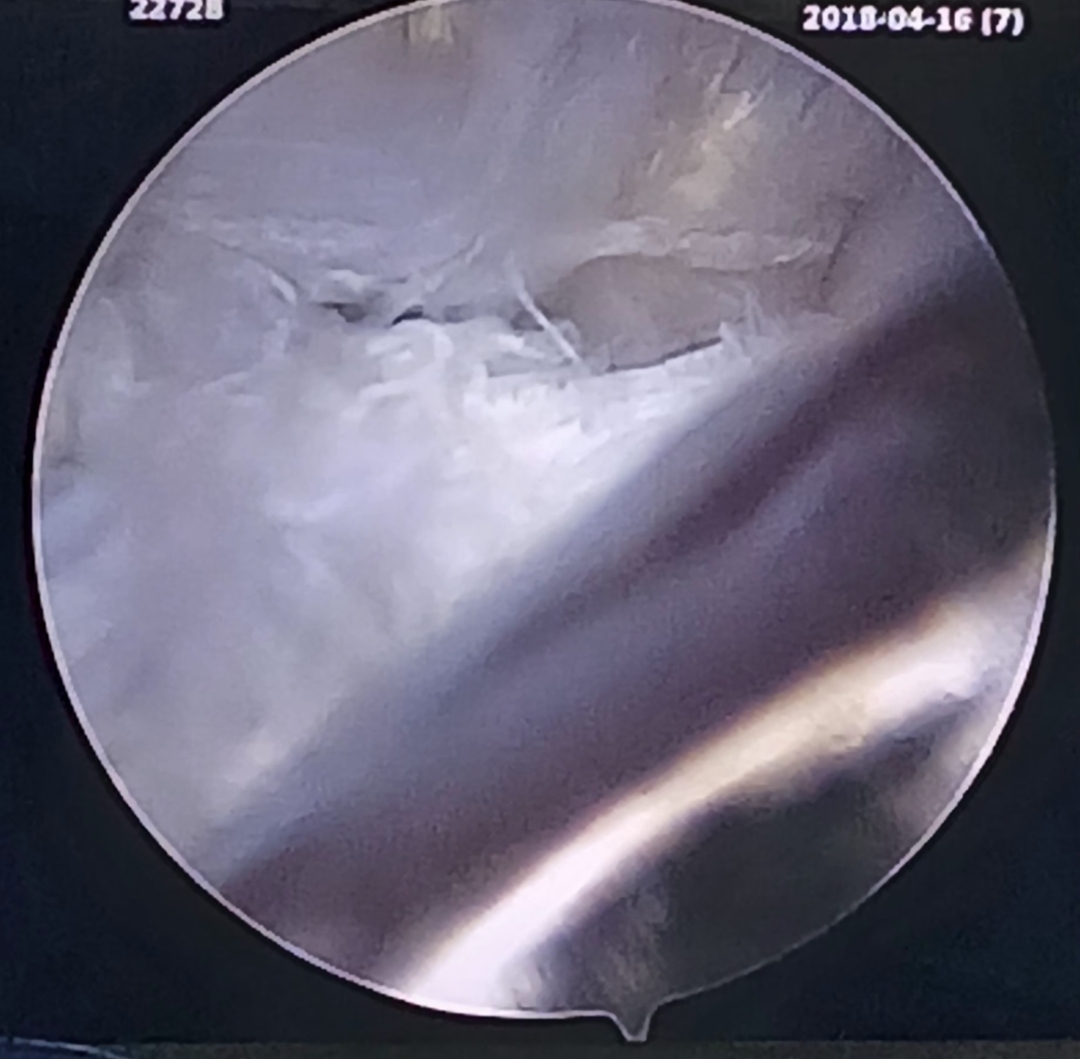

Hello everyone, this week, I got to be with surgery again. It was not a very busy week but I got to see a few good cases. The most popular surgery this week was a TPLO which is where they added metal plates to the bone of the dog to help with their torn ligaments and meniscus. There was another surgery case with a dog named Bennett that I first met with the oncology department. They had to take a CT scan to find a tumor in the dog so they got the help from the surgery team to remove it. While it was a small tumor, since it was on the pancreas, it caused the dog to develop diabetes. The surgery could not garentee that removing it could improve the diabetes so they sent him to the ER department to be monitored over the weekend. On that day, I also got to see a splenectomy, where they removed the spleen because it had a tumor and they had to tie the stomach to the side. Dr.Nye found a small skin tumor that she removed. However, while suturing it, the dog almost woke up which scared me but they handled it very well. Since it wasn’t too busy, I got to go home earlier than expected so I had to take a Lyft to my sister’s campus and to the apartment. On Friday, my sister took me to see the lights at Bright Nights which was pretty fun to see. Then she went camping Saturday so I was by myself for the majority of the day. It was a pretty fun week and I am excited about what I get to learn from the Emergency and Critical Care department.